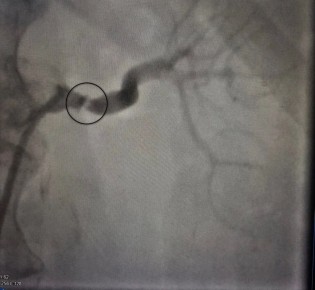

У 57-летней женщины была сужена левая почечная артерия, что привело к тяжелой, невосприимчивой к многокомпонентной медикаментозной терапии артериальной гипертензии. У женщины также было ожирение и сахарный...

Воронежские врачи успешно диагностировали и вылечили

редкую патологию у 57-летней женщины. У нее была сужена левая почечная артерия,

что привело к тяжелой, невосприимчивой к многокомпонентной медикаментозной

терапии...